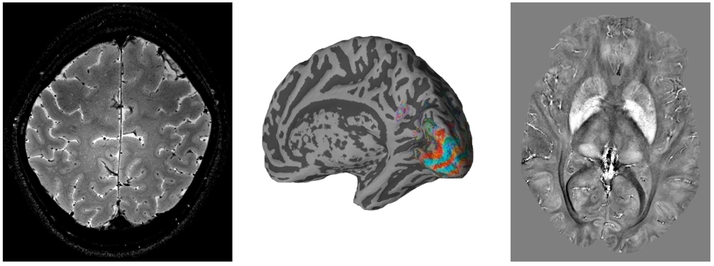

High resolution anatomical and functional brain images produced on the 7T scanner